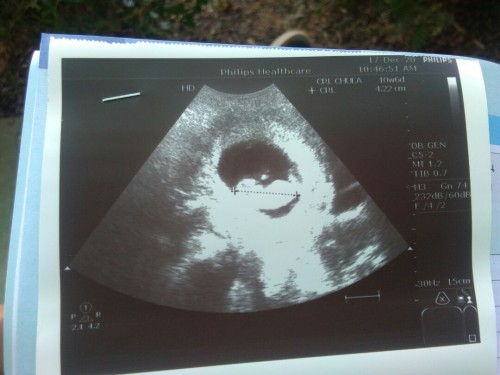

9w4dจ้า